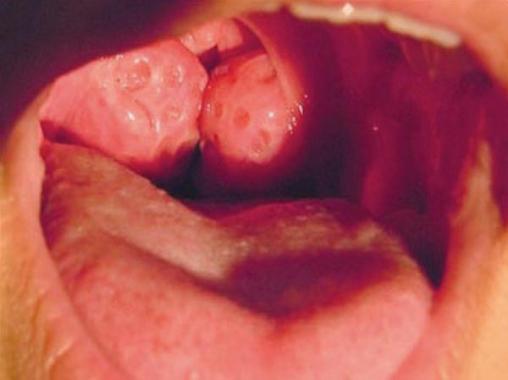

L’amygdale en elle-même est une formation lymphoïde appartenant à l’anneau de Waldeyer. Contrairement aux végétations adénoïdes, elle est présente dès la naissance, de consistance plus ferme, limitée en dehors par une capsule et parsemée de cavités encore appelées cryptes. Entre la capsule et le fascia pharyngo-basilaire, il existe un espace décollable appelé espace péri-amygdalien impliqué dans les complications des angines.